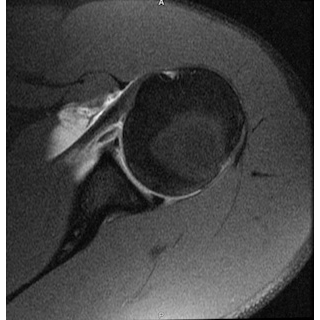

| Tackling Trauma: Recurrent Shoulder Injuries In A Football Athlete - Page #3 | |||